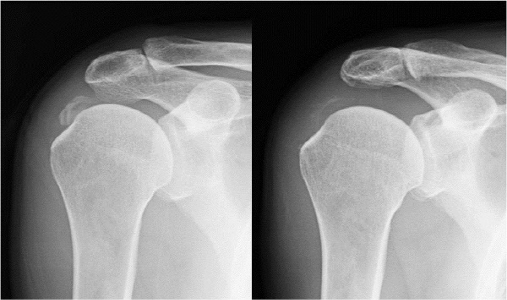

석회화건염 환자에 대한 체외충격파 시술 전(좌측)과 후 사진.. 딱딱한 석회가 수차례 체외충력파 시술후 완전히 분쇄돼 깨끗한 모습(우측)을 보이고 있다.

석회화건염 치료는 비수술 치료와 수술 치료로 나뉘는데, 비수술 치료로는 주사치료와 체외충격파를 들 수 있다. 주사치료는 강력한 소염제인 스테로이드 약물을 석회 병변에 주사해 석회를 녹여 흡수시키는 치료법이다. 체외충격파는 석회 침착물에 충격파를 이용해 외부에서 충격을 가해 내부의 석회를 잘게 분쇄시키는 치료다. 환자가 느끼는 통증이 비교적 덜하고, 대략 5-10분이면 치료가 끝나나 수차례 반복을 해야 한다.